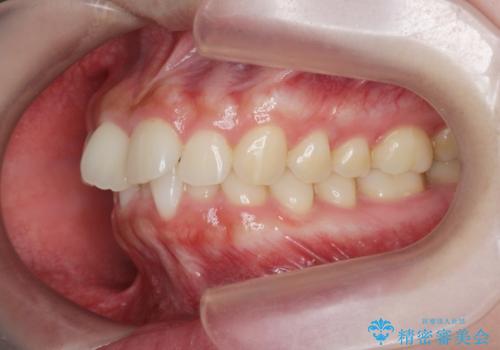

マウスピース 狭窄歯列の改善

- 噛み合わせが深い、笑った時の歯並びの改善を求めて来院されました。

マウスピース型の矯正装置インビザラインを用いた治療を計画します。

狭くなってしまった歯並びを放物線状に並べることで噛み合わせの安定・見た目の改善・ガタつきの改善を達成することができました。